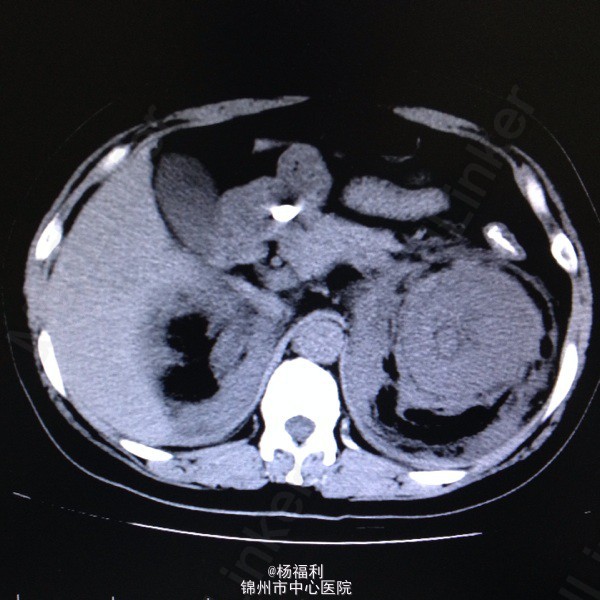

44岁女患。为消化科我会诊患者。 现病史:以上腹痛9小时为主诉入院。无发热及寒战、噁心未呕吐,无腹泻及黑便。 既往史:双眶炎性假瘤2年,口服激素治疗,并补钾。

查体:上腹部压痛,无反跳痛、右侧压痛明显,右肾区叩击痛,左肾区轻叩击痛,双输尿管走形区无压痛。 辅助检查;泌尿系彩超:双肾积水。 血白细胞:9.99*10^9。 肾功能正常。 全腹部ct及MRU检查:见图片。

诊断;真的不知道是啥病。 处理:暂时止痛处理。双肾病变。不知从哪里下手。